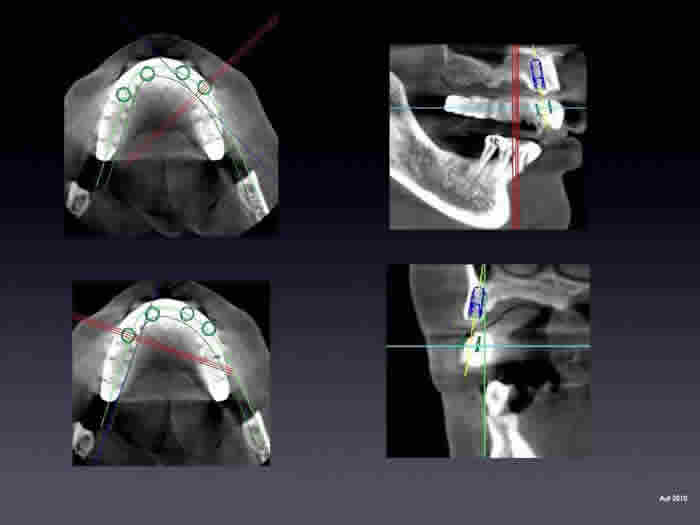

CT scans also allow us to do Guided Implant Surgery. With a detailed 3d view offered by the scan, we can position implants on a computer then transfer the exact position to the patient mouth and many times without even a surgical incision. This is one of the most exciting advances in dentistry and we have had fantastic outcomes. Below is an example of computer placement of implants.